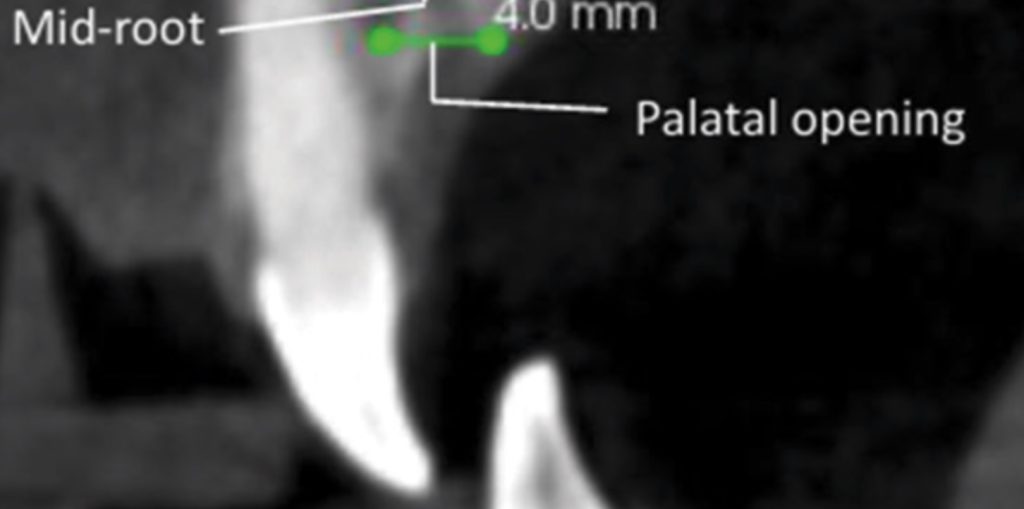

- Retracción con implantes: Explica cómo se utilizan los microimplantes para la retracción en masa en casos de extracciones, clasificando la mecánica según la altura del microimplante en relación con el plano oclusal (tracción baja, media y alta), y cómo esto influye en la rotación del plano oclusal mandibular y maxilar.